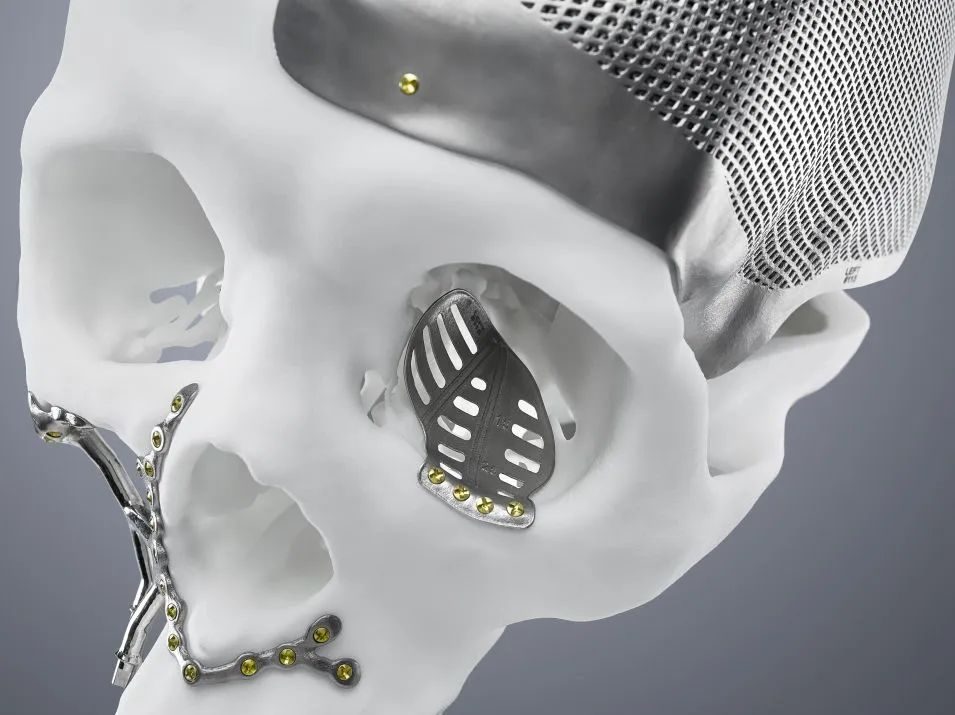

CMF 植入物指的是用于面部和颅骨区域的医疗植入物,主要用于修复和重建因肿瘤、外伤或萎缩引起的先天性或后天性畸形。

通过与通快的合作,KLS Martin Group 成功借助 TruPrint 2000 生产出了适合患者需求的高质量植入物。这些高精度的植入物不仅提高了手术的成功率,还显著缩短了患者的康复时间,减少了患者的手术次数和风险。